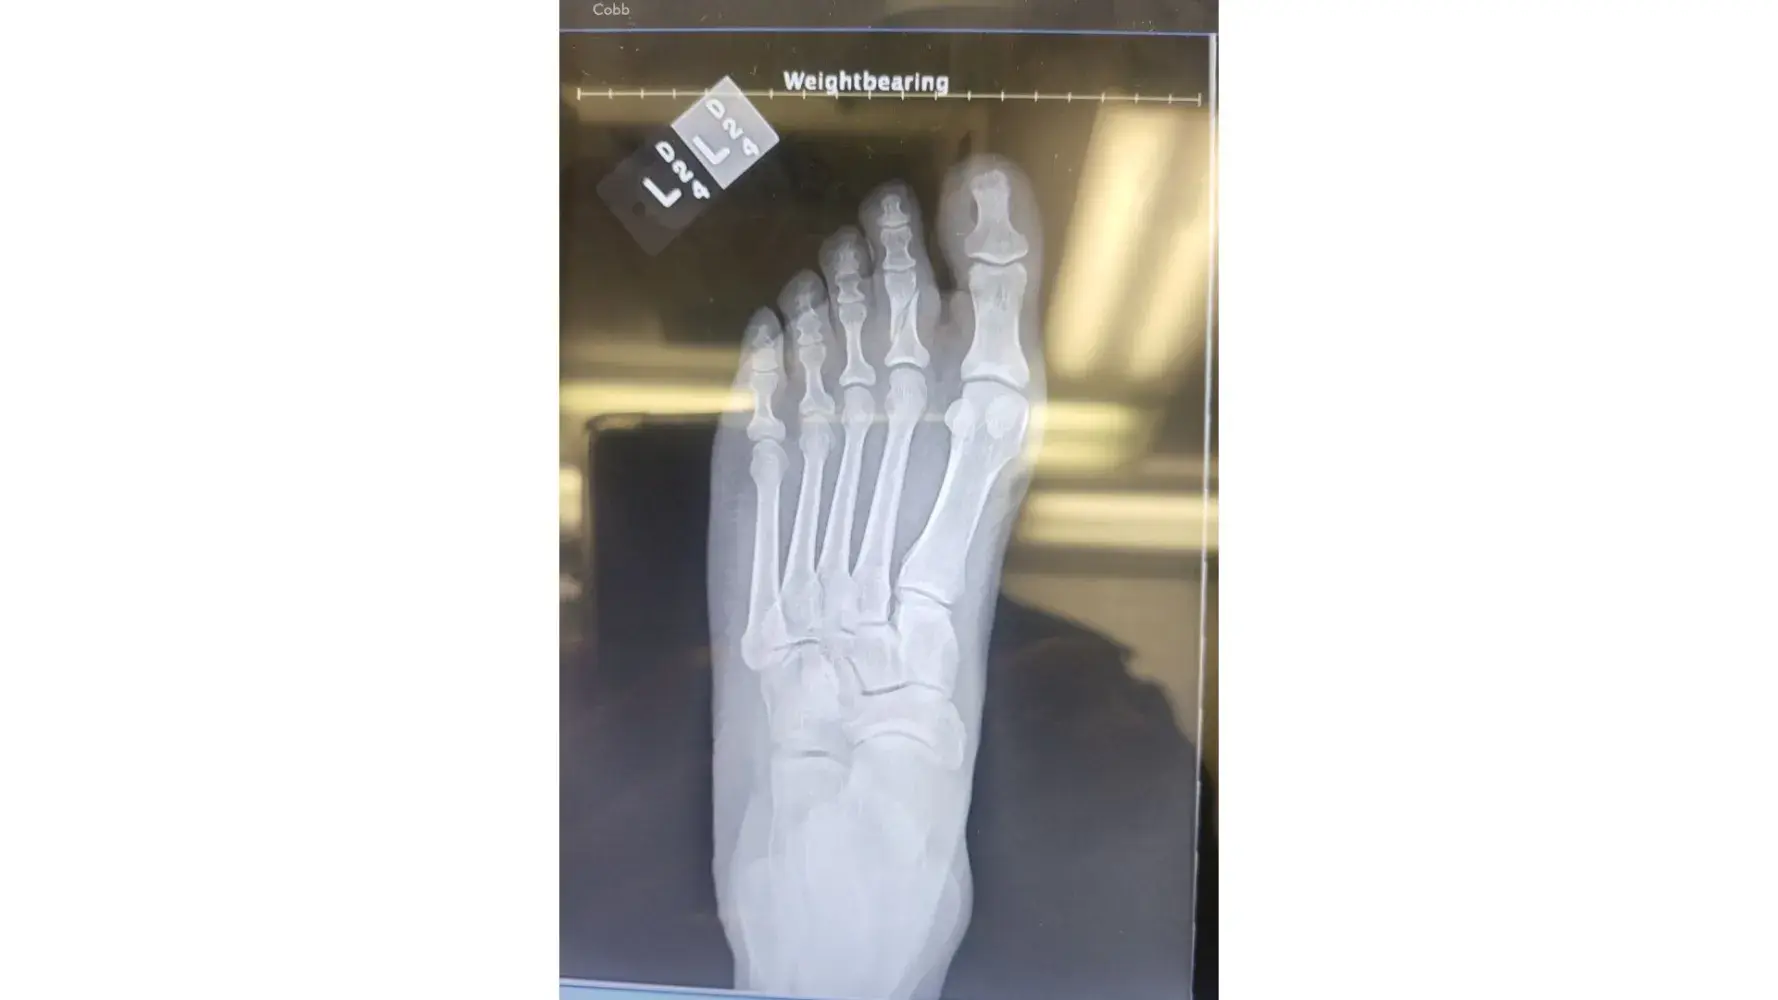

I checked in the resort on December 1, 2022. I prepaid for a Marvelous suite Months ago to celebrate my Birthday in Panama City. When I entered the room #1923. I went to sleep after a long day of travel. As the daylight began to come through the patio door I got up to close the curtains. Without realizing the sofa bed (let out murphy bed) between the King bed and patio door was broken and protruding out at the bottom. This area should've been flush to the sofa. My foot hit the edge of this and caused severe pain. I laid back down until morning break. I called down to the hotel lobby from the room to report what happened. I was instructed someone would be coming up to take a look. No one ever showed up. Later in the day (Dec. 2nd) after elevating my leg in the room I came down to speak with someone at the desk. A report was made in the resort computer By Domingo. I also spoke with David about the matter. Maintenance was asked to go to the room to fix the sofa and ice was sent up. It was a failed attempt, the piece still protruded away from the sofa. I asked for a Manager, I was told he would not be in until the next morning. In the meantime An EMT from the resort was asked to come look at the foot. She did a quick look and concluded it was NOT fractured but bruised. Her Recommendation was to ice and elevate the foot and to stay off of it. She said it will hurt and stay swollen for a few days. This was not my idea for a vacation. The next morning (Dec. 3rd) I stopped at the desk limping. My entire foot was swollen and throbbing. I spoke to David again and showed him my swollen foot from the injury. I waited for the Manager to become available. He spoke with me and apologized for the inconvenience. He offered to move me to another room which I did to avoid any further injuries. On Dec 4th I checked out. I When I arrived home I still had pain and trouble walking but expected to get better according to the Resorts EMT. On December 14th, 2022 I went to the Friends Family Health Clinic because there was no relief. The Nurse indicated that the swelling would have gone down before now if it was only bruised and ordered an Xray. I went directly to the University Of Chicago Hospital for the Xray. I received a call shortly after arriving back home from the Doctor, he confirmed that the left foot 2nd toe is fractured. (broken). This has caused me PAIN & SUFFERING. It has been difficult to function daily duties at home or work.

Desired outcome: Refund for entire stay at the RIU and reimbursement for prepaid activities that I could not enjoy. Doctor visits. Pain & Suffering. Total $5,000.00Monica J Allen708-945-9925

Update by Monica J Allen

Dec 15, 2022 12:19 pm UTC

photos from Xray